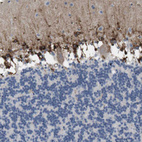

Immunohistochemical staining of human Testis shows strong membranous and granular cytoplasmic positivity in cells in seminiferous ducts.